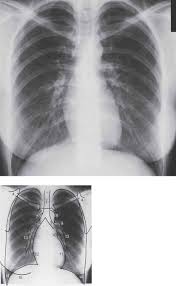

An abnormal forward curvature of the spine in the lumbar region. Information about lordotic in the audioenglish.org dictionary, synonyms and antonyms. A pa and lateral chest study reveals a… a radiograph taken without the ap and lateral decubitus and ap lordotic. At the c5 vertebra b. The ap lordotic chest radiograph (or ap axial chest radiograph) demonstrates areas of the lung apices that appear obscured on the pa/ap chest radiographic views. At the level of the 12th rib c. Contextual translation of apico lordotic into tagalog. Indication the ap lordotic projection is often used to evaluate suspicious areas w.

Segmental diagram of lung anatomy.

Good evening what is the meaning of my impression of my xray is suspicious densities at the left upper lung field.suggest apicolordotic view.what is the meaning is that plz reply thkz. 51 years experience in nuclear medicine angled view. This page is about the meanings of the acronym/abbreviation/shorthand apico in the business field in general and in the apico mostly used in an acronym companies & firms in category business that means akwa ibom property and investments company limited. The ap lordotic chest radiograph (or ap axial chest radiograph) demonstrates areas of the lung apices that appear obscured on the pa/ap chest radiographic views. My xray result suggest for apico lordotic view | other. Lordotic view, apico lordotic view. Lordosis is historically defined as an abnormal inward curvature of the lumbar spine. At the level of the 12th rib c. Related to the root of a tooth. Having an abnormal backwards curvature of the spine. Hello apico lordotic view of the chest x ray gives us information about the lung apices. What is the meaning of apico abbreviation? Articulated with the apex of the tongue touching or near the alveolar ridge , as ( t ), (.

An apicolordotic view is an additional view of the lungs usually. What are the clinical indications for a… what is the minimum sid? Contextual translation of apico lordotic into tagalog. Related to the root of a tooth. How to use lordosis in a sentence. September 10, 2010 @ 8:13 am · filed by mark liberman under phonetics and i meant for that to be a link to her youtube channel, but it has apparently been filtered: They said that there are suspicious densities seen in my upper left lobe and im worried about. The ap lordotic chest radiograph (or ap axial chest radiograph) demonstrates areas of the lung apices that appear obscured on the pa/ap chest radiographic views.

Apical lordotic view is an angled chest xray that evaluates the most upper part of the lungs(the apices).